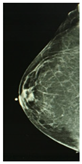

According to the Breast Imaging Data and Reporting System (BI-RADS), a PBD increase along a three-year period is associated with a higher breast cancer risk, and a PBD decrease with a smaller risk, than the risk when PBD remains unchanged. Two longitudinal BI-RADS breast density measurements (on current and previous mammography) may be better predictors of breast cancer risk than a single measurement [14]. The incorporation of breast density to the Gail model, a mathematical instrument that measures the risk of developing breast cancer in five years by identifying risk factors [15], increases predictive accuracy by statistical agreement from 0.607 to 0.642 [16]. The PBD BI-RADS classification is defined in Table 1, where illustrative cranio-caudal (CC) and mid-lateral oblique (MLO) mammography imaging samples for right and left breast are shown.

Table 1. BI-RADS classification and its relationship with mammography.

BI-RADS PBD ClassificationMammography

Right

(CCR)

Left

(CCL)

(MLOR)

(MLOL)

a = 0–25%

(Homogeneous adipose)

Sensors 22 02747 i001 Sensors 22 02747 i002 Sensors 22 02747 i003 Sensors 22 02747 i004

b = 25–50%

(Heterogeneous dispersed)

Sensors 22 02747 i005 Sensors 22 02747 i006 Sensors 22 02747 i007 Sensors 22 02747 i008